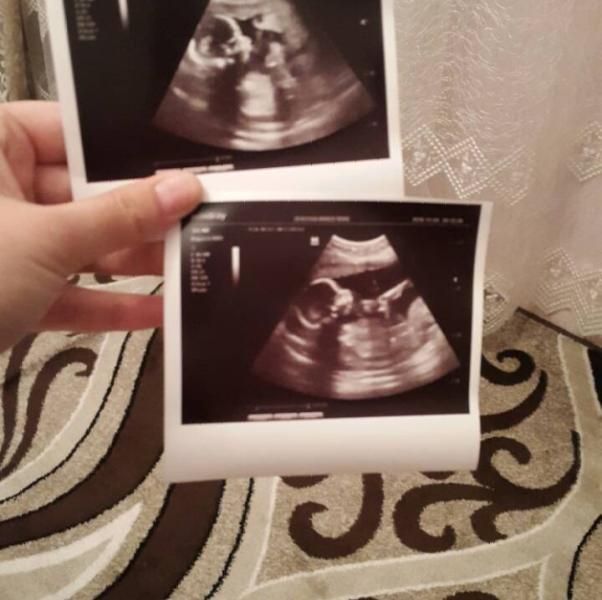

Ходили на -УЗИ- осмотреть здоровье ребеночка😘😍) Меня обрадовала новость, то что у нас будет ДЕВОЧКА🙈😇❤, у нее со здоровьем все хорошо🤗... Палец сосет, обжорочка моя 😹😻)))

@darina1993 спасибо)) да пожалуйста, 1-й род-дом, Зарина Нарзулаева 🖒) она на 12 недели беременности точно говорит пол ребенка😊